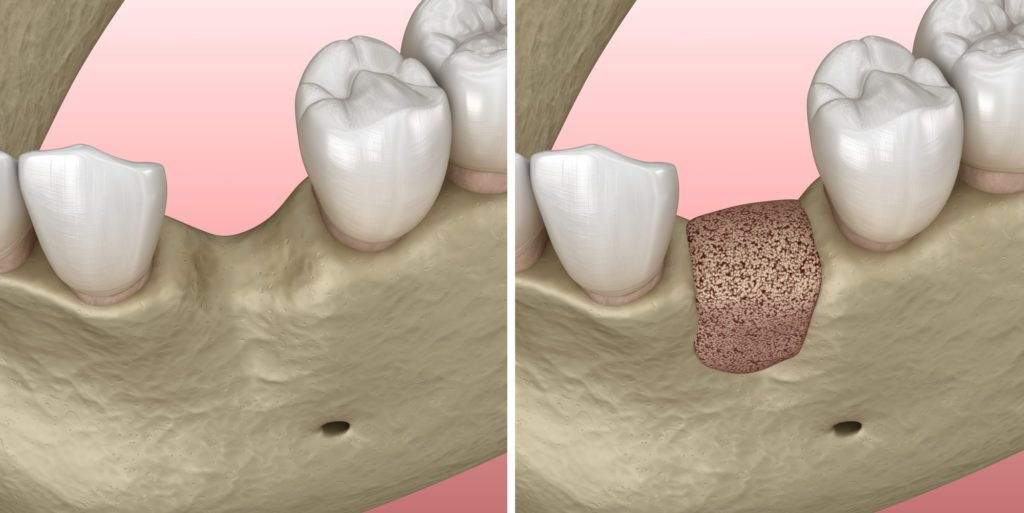

زراعة عظم الفك هي إجراء طبي يهدف إلى زيادة كثافة وسمك العظم في الفك لتحضير المنطقة لتركيب غرسات الأسنان بشكل آمن وثابت، تتم العملية باستخدام مواد عظمية طبيعية أو صناعية، وتساعد على تعزيز دعم الغرسات وتحقيق نتائج طويلة المدى.

تعتبر زراعة عظم الفك خطوة أساسية الأمر الذي يضمن نجاح عملية زراعة الأسنان، خصوصًا في الحالات التي تعاني من نقص العظم بسبب التسوس، أمراض اللثة، وفقدان الأسنان لفترات طويلة من أهميتها:

هل يمكن استبدال عظم الفك؟

نعم يمكن استبدال أو تعويض عظم الفك في حالات معينة من خلال إجراءات طبية متقدمة تعرف بزراعة عظم الفك أو ترقيع العظم، هذه العملية تهدف إلى استعادة حجم وكثافة العظم المفقود في منطقة الفك لضمان ثبات الغرسات ونجاح عملية زراعة الأسنان، عادة ما يلجأ إلى استبدال عظم الفك في بعض الحالات مثل فقدان الأسنان لفترة طويلة أدى إلى تراجع العظم، الإصابات أو الحوادث التي تسببت في تآكل العظم، أو حالات أمراض اللثة المتقدمة التي أدت إلى فقدان جزء من العظم الداعم للأسنان.